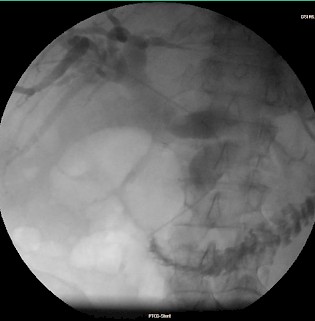

Fallbeispiel:

Patient mit Pankreaskopf-Ca, Leber- und Lungenmetastasen und Tumorverschluß des Gallengangs: